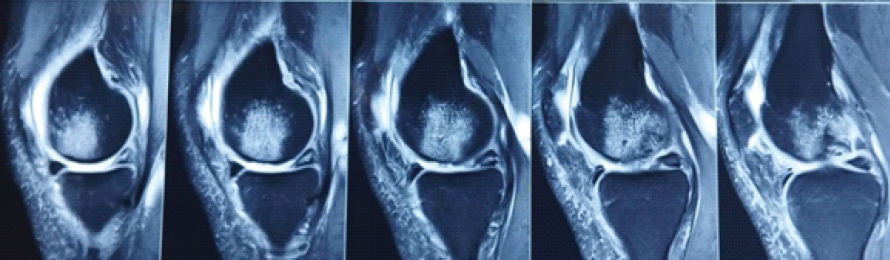

Figure 1: Pre-operative magnetic resonance imaging showing cartilage lesion of the medial femoral condyle.

We initiated the arthroscopic autologous MCI technique with a diagnostic arthroscopy to assess the cartilage defect. Healthy cartilage was then arthroscopically harvested from the defect using a soft tissue shaver connected to an autologous tissue collector (GraftNet: Arthrex), ensuring minimal enlargement of the defect after preparation. The calcified layer was removed, but subchondral drilling was not performed. The harvested cartilage was minced into small fragments, resulting in a paste-like consistency. Minced cartilage was then mixed with platelet-rich plasma (PRP) in a 1:3 ratio. The resulting mixture was loaded into an applicator. Autologous thrombin was generated from additional PRP using a specific device (Thrombinator: Arthrex). After thoroughly drying the joint, the defect was filled with the cartilage-PRP mixture using the applicator. Following a short waiting period, the knee joint was moved through a range of motion to confirm graft fixation over the chondral defect (Fig. 1, 2, 3, 4).